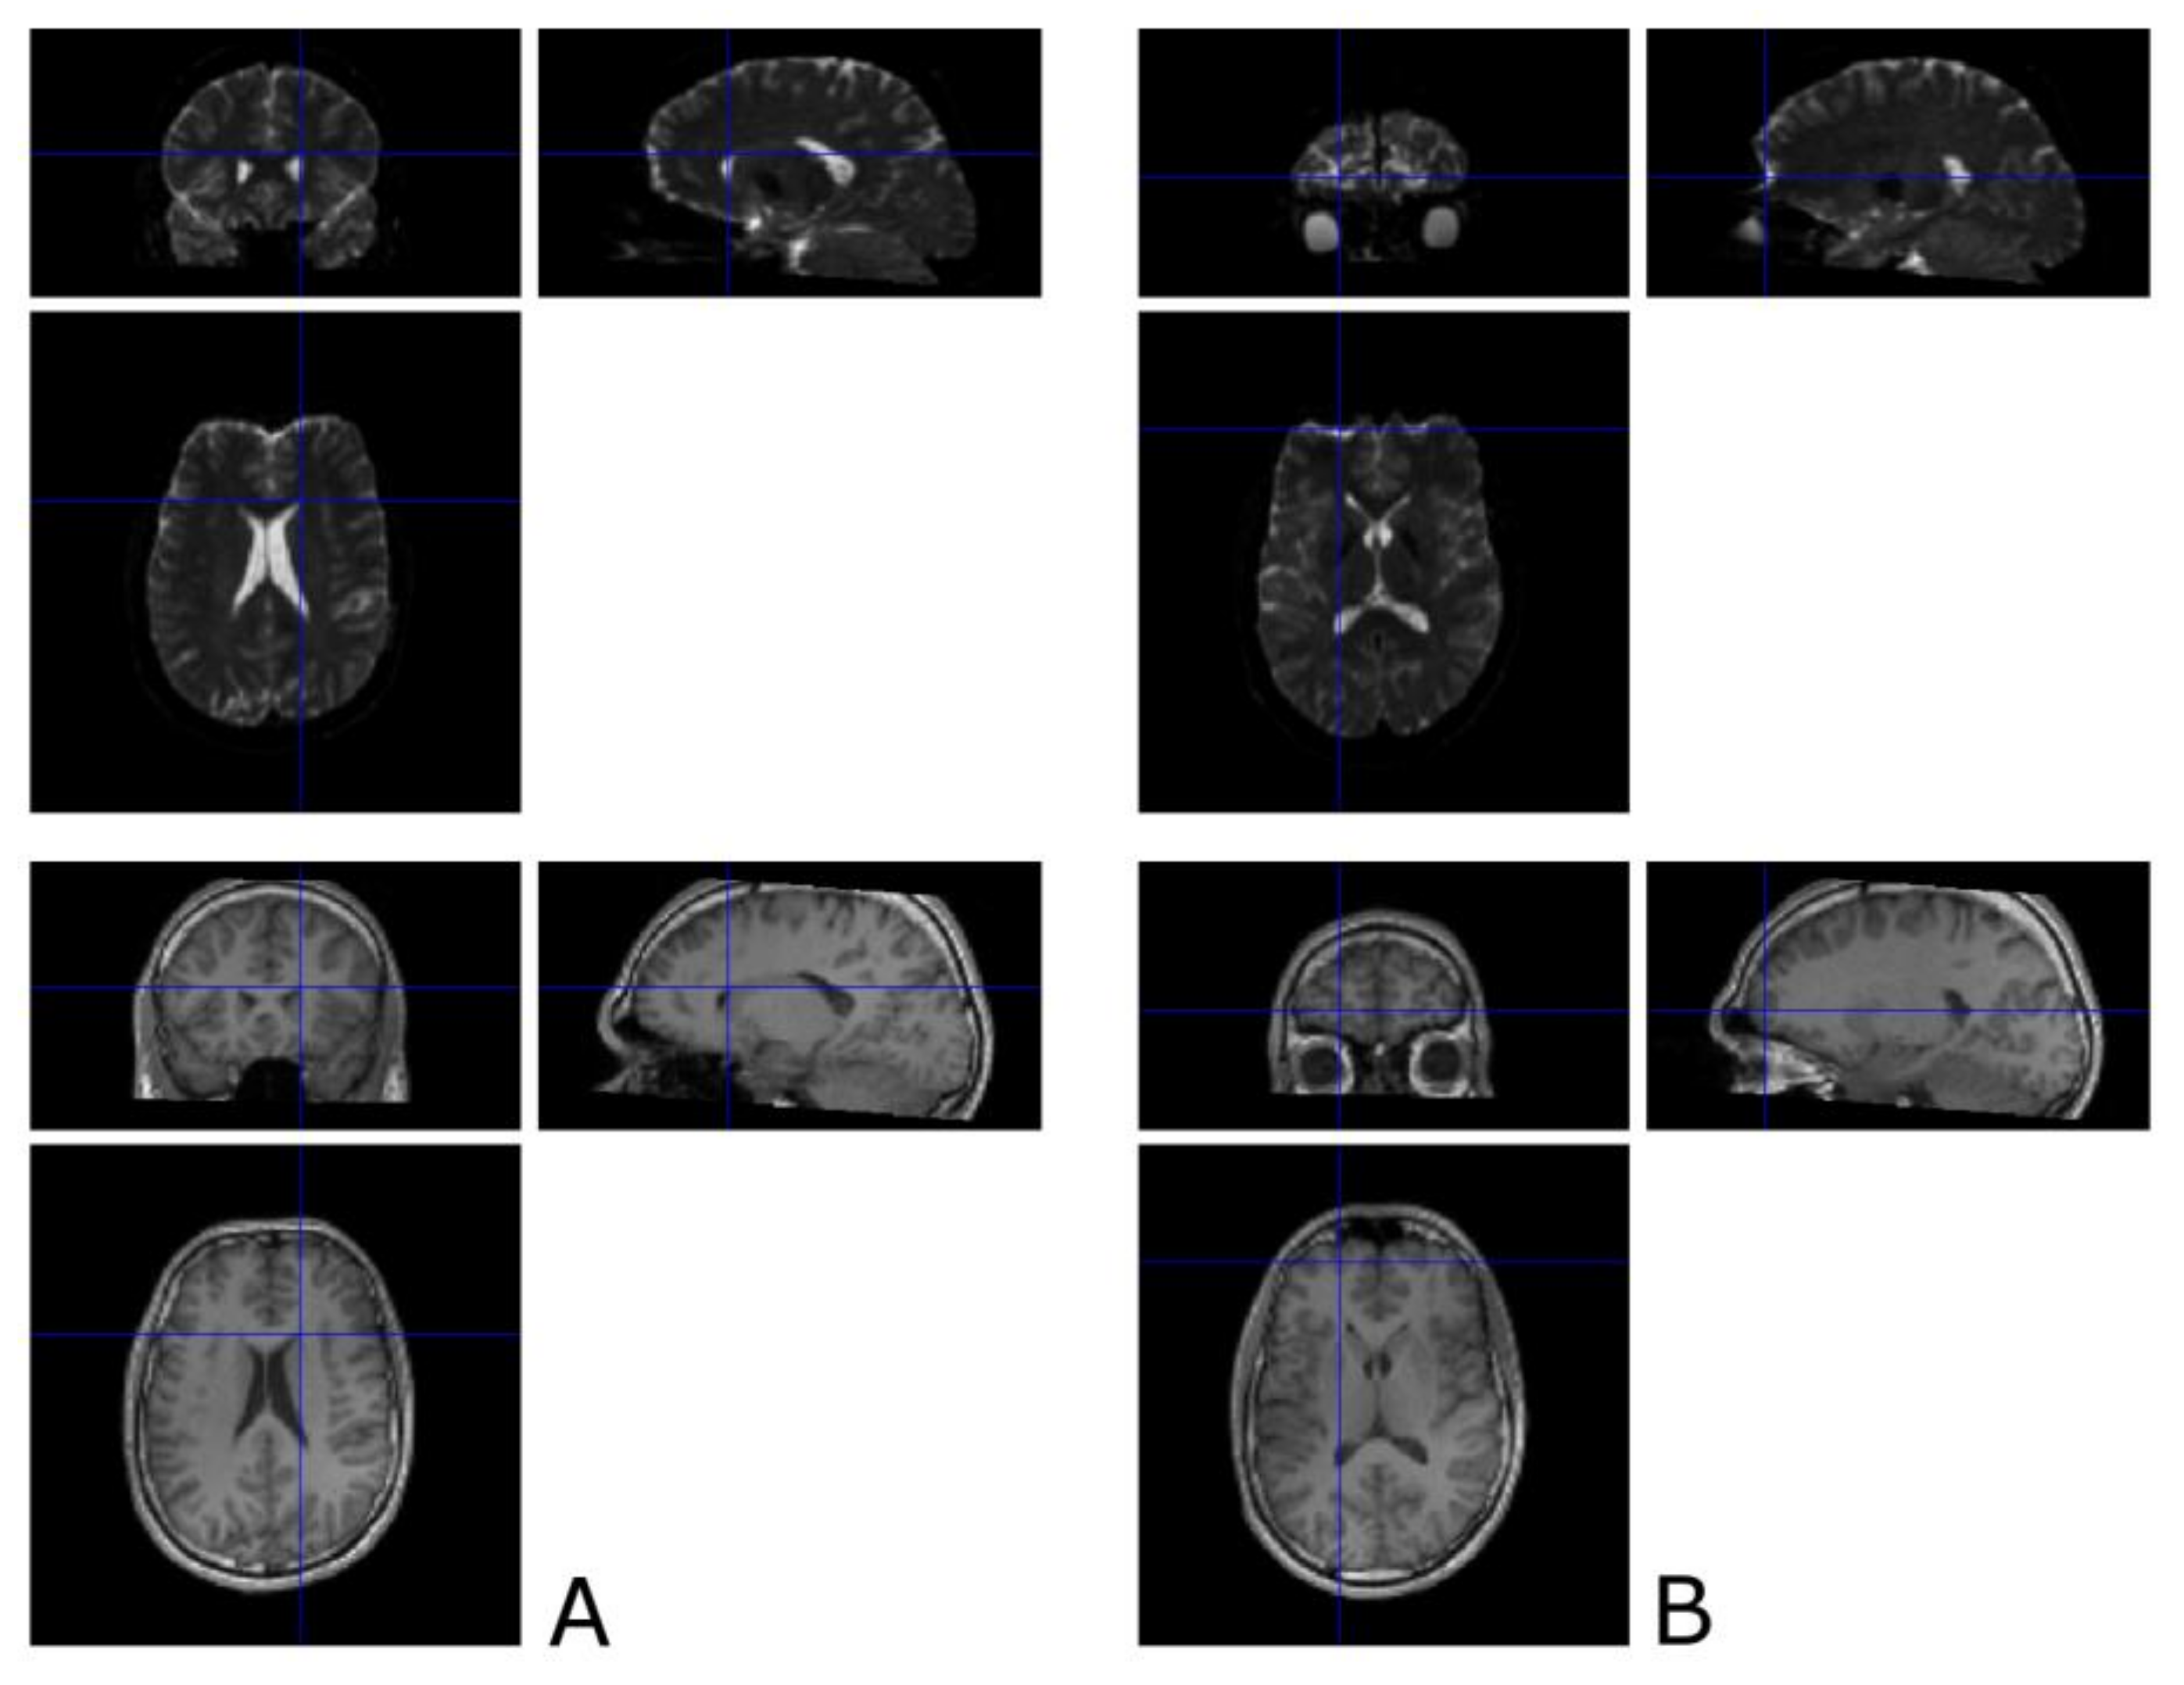

3.1. The Corticospinal Tract

3.2. The Optic Radiation